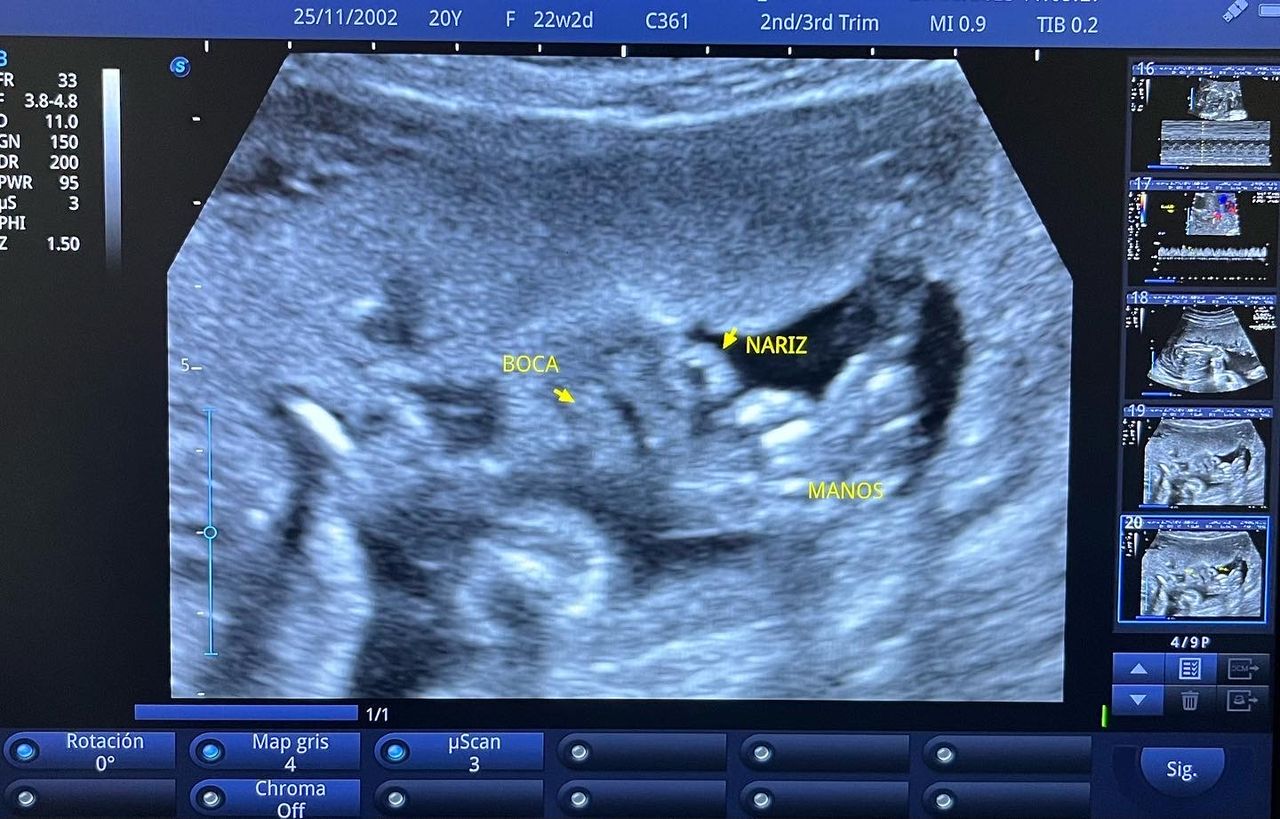

Médico general con 15 años de experiencia, master en enfermedades infecciosas y antibioticoterapia por parte de la Universidad Cardenal Herrera en Valencia, ademas de diversos diplomados en el área de Infectología y Parasitología, Urgencias, Imagenología y Medicina del Trabajo. He laborado en Hospitales y Clínicas en el área de Urgencias, en Laboratorios realizando estudios de Imagen, en especifico ultrasonidos de todo tipo desde básicos hasta avanzados incluidos los obstétricos estructurales, en Secretaría de Salud del Estado de Querétaro realizando ultrasonidos obstétricos para la detección de malformaciones en los tres trimestres del embarazo en diversos centros de salud, como médico de Empresas en el campo de Salud Laboral y actualmente en este consultorio en donde para su mejor atención y siempre buscando integrar la mayoría de las herramientas diagnosticas cuento con equipo de ultrasonido como apoyo en la exploración del paciente o como servicio diagnostico por imagen, realizo ultrasonidos convencionales (hepatobiliar (hígado, páncreas, vesícula y bazo), vías urinarias, ginecológico abdominal y transvaginal, tiroideo, prostático, testicular, pared abdominal) y especializados (dopler obstétrico en los 3 trimestres de embarazo), musculoesquelético en lesiones deportivas. También cuento con un equipo de electrocardiograma de 12 derivaciones para monitoreo completo del funcionamiento cardiaco, espirometria para evaluar la función pulmonar en la consulta, pruebas rápidas que se realizan en consultorio para detectar de forma mas precisa enfermedades infecciosas como Influenza A y B, covid19, infecciones urinarias, dengue, zika, chikungunya. Cuento con diversas vacunas para prevención de enfermedades. Siempre con el objetivo de dar el mejor servicio y atención a su salud. Lo espero en consulta para escucharlo y estudiar su caso de la forma más completa posible, estoy seguro de que tendremos las mejores opciones para su tratamiento. Mi tranquilidad es que usted se vaya con todas sus preguntas e inquietudes resueltas.

• Ultrasonido obstétrico